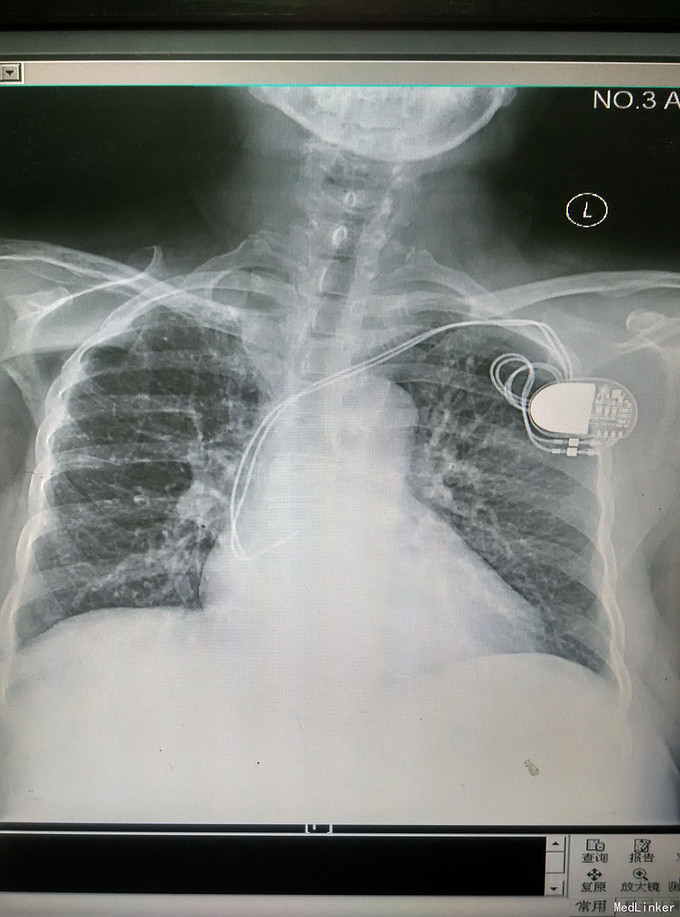

主动脉瓣关闭不全x线

主动脉瓣关闭不全x线,

轻度主动脉瓣狭窄伴中度主动脉瓣反流,升主动脉增宽;3.

肺血增多主动脉瓣关闭不全,平时一般无症状,但一旦发病,病程进展很快

入院后心超检查示"风湿性心脏病,主动脉瓣狭窄(重度,关闭不全(轻度

x射线影像图中可见行置换术后的二尖瓣和主动脉瓣.

诊断 处理诊断:心脏瓣膜病 主动脉瓣钙化(并轻中度